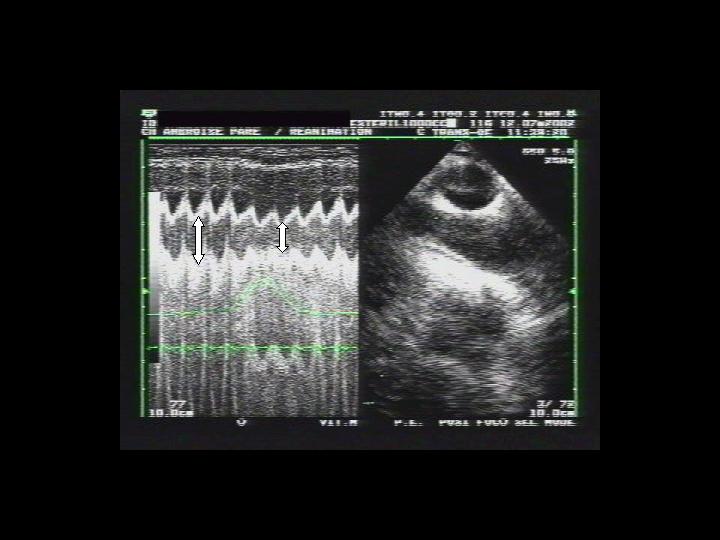

Longitudinal view of the superior vena cava by transesophageal route, in 2D mode coupled to M-mode, in a patient on assisted ventilation presenting no respiratory variation in the diameter of the superior vena cava.

Figure 1 : the pressure signal in the airways appears in green on the screen.

Maximal and minimal diameters are indicated by the arrows.